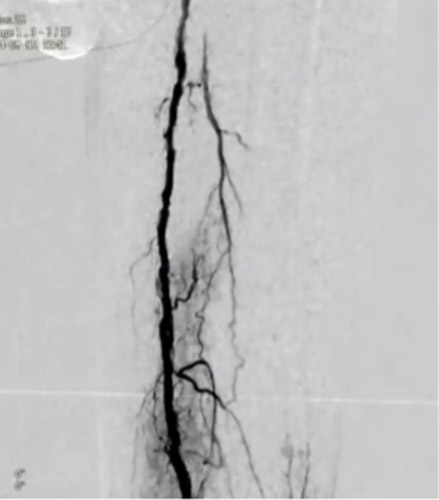

同側順行アプローチにて造影を行うと前回治療したPA(Peroneal Artery)は開存しており、ATA(Anterior Tibial Artery)は入口部から閉塞していた(図1)。末梢部分のDA(Dorsal Artery)は確認出来た(図2)。